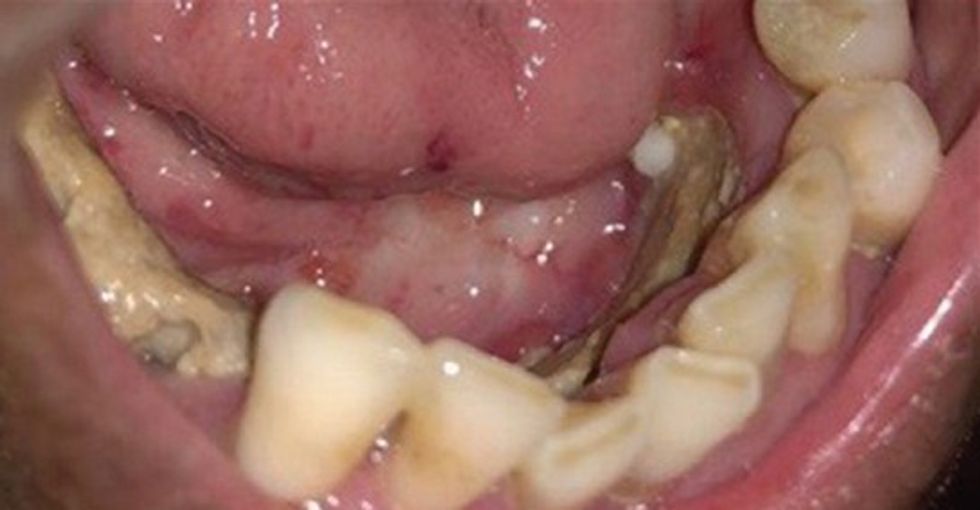

Komplikimet orale ndodhin në forma dhe shkallë të ndryshme. Disa ndodhin gjatë trajtimit, të tjerat pas disa viteve. Fatkeqësisht, të sëmurët me kancer shpesh nuk marrin kujdes adekuat të dhëmbëve derisa të shfaqen ndryshime serioze.

Kariesi

Kariesi pas rrezatimit ndodh kryesisht si rezultat i tharjes së gojës dhe ndryshimeve cilësore në përbërjen e pështymës.